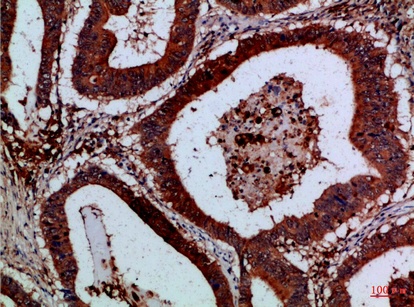

Fig.1. Immunohistochemical analysis of paraffin-embedded Human-colon-cancer, antibody was diluted at 1:100.